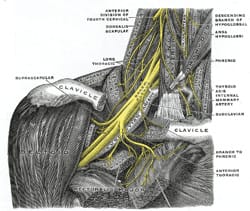

1861

Holmes Coote

Holmes Coote performed the first TOS surgery. A 26 year-old female servant described a hard mass in her left lower neck, present since childhood. The “tumor” had grown recently, and she experienced paresthesias in the tips of her fingers, with loss of pulses at the wrist, wasting of muscles in the arm, and weakness leading to dropping of items. Mr. Coote explored the area while the patient was “fully under the influence of chloroform.” He noted a bony ‘tumor,’ which he had to divide from the cervical vertebra. He also found it was attached to the first rib anteriorly. He removed as much of the ‘tumor’ as he could, and pulses returned in the left upper extremity. Coote described his trepidation at exploring this area thusly: “But the region was not a pleasant one for any proceeding demanding the use of the knife. The subclavian artery and vein were in front; the axillary plexus of nerves lay spread out above; below, the apex of the lung, covered by the pleura, rose up in dangerous proximity; on the scalenus was the phrenic nerve; while towards the mesial line were the important vessels and nerves passing to the head, together with the vertebral vessels and thoracic duct. You can understand, therefore, why I was cautious in what I did.” The bony tumor was referred to as “an exostotic growth from the transverse process of the seventh cervical vertebra,” and “a development of the costal element, the rib, of the seventh cervical vertebra.” Thus, Coote became the first person to surgically treat a TOS patient.

Thomas Wingate Todd at Manchester University describes the potential causes of neurovascular compression in the thoracic outlet in a series of scientific papers outlining the anatomy and anatomical variations of the thoracic outlet. Dr. Todd’s anatomic dissections included descriptions of cervical ribs, anatomic variations of the first rib and scalene muscles, and the position of the clavicle with shoulder movements. Dr. Todd also postulated that the gradual descent of the shoulder girdle with aging causes narrowing of space between the clavicle and rib, contributing to neurovascular compression. However, Todd also describes in detail a distinct mechanism causing narrowing of only small, distal arteries. In 1912, he shows sympathetic nerve fibers passing from the T2 nerve root to the T1 nerve root variably in humans. In 1913, he demonstrates that pressure on sympathetic nerves causes narrowing and occlusion of small arteries. Dr. Todd became Professor and Chairman of Anatomy at what is now Case Western Reserve University Medical School in Cleveland in 1912. Dr. Todd built the Hamann-Todd Osteological Collection, the world’s largest collection of human and anthropoid skeletons. He also publishes The Atlas of Skeletal Maturation in 1937, and initiated the Brush study in 1926, both of which are widely-accepted tools for the evaluation of human skeletal growth and maturation.

John Sebastian Bach Stopford and E. D. Telford at Manchester University Medical School describe compression of the lower trunk of the brachial plexus by a normal first rib, and report results from 10 patients following resection of the first rib. Stopford and Telford considered the following three key elements as the underlying etiologic factors in development of brachial plexus compression:

- Anatomical relationship of the brachial plexus and the first rib, including anatomic variations of the first rib

- Gradual descent of the shoulder from childhood to adulthood

- Strength and tone of the supporting muscles of the shoulder

Stopford and Telford reported the first case of a patient with neurogenic symptoms and a cervical rib, in whom successful treatment was performed by resection of the normal first rib, leaving the cervical rib in place.

John Sebastian Bach Stopford trained under Thomas Wingate Todd, and wrote numerous scientific papers on the traumatic disruption of nerves, the regeneration of injured nerves, the autonomic nervous system, and the compression of peripheral nerves, most notably that caused by cervical ribs.

1929

Howard Christian Naffziger and Francis Clark Grant

Naffziger and Grant first introduce the concept of neurovascular compression in the thoracic outlet due to scalene muscle anomalies, without the presence of a cervical rib. They perform the first scalenotomies in patients without cervical ribs, but do not publish their findings until 1937 and 1938. Dr. Howard Christian Naffziger, who trained under eminent surgeons William Halsted and Harvey Cushing, became one of the most esteemed neurosurgeons of his time. He created the division of Neurosurgery and served as Chairman of the Department of Surgery at the University of California San Francisco, was elected president of the American College of Surgeons, and was Chairman of the committee that established the American Board of Neurological Surgeons. Francis Clark Grant trained under eminent neurosurgeons Charles Frazier and Harvey Cushing. Dr. Grant succeeded Dr. Frazier as Professor and Chairman of Neurosurgery at the School of Medicine and the University Hospital at University of Pennsylvania. He published over 200 papers in his lifetime, and refined or developed several neurosurgical procedures and instruments.